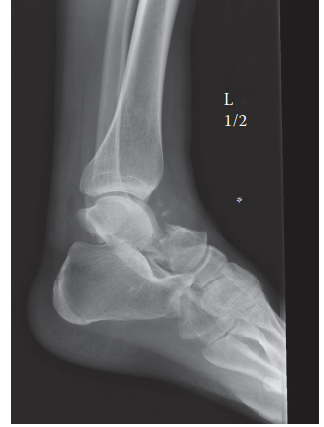

A 76-year-old non-insulin dependent diabetic returns to your clinic 3 weeks after ORIF of a right ankle fract…

Can you describe the radiograph? This is a lateral radiograph of the left ankle showing a displaced talar nec…